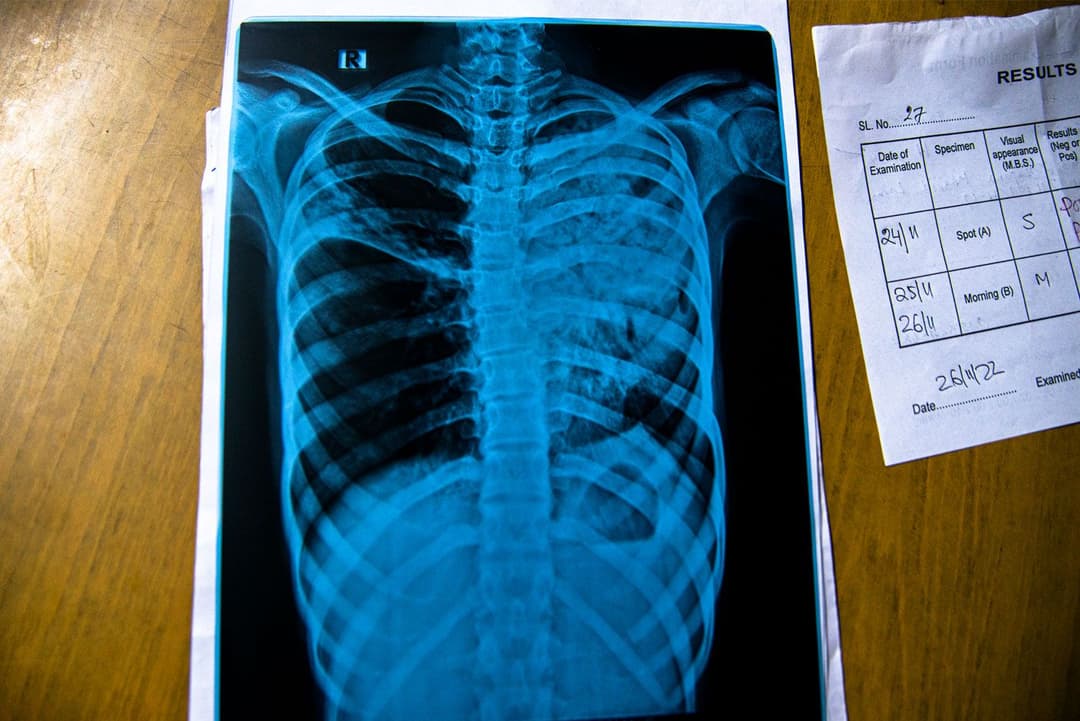

ప్రైవేట్ వైద్యశాలలకు వెళ్ళే స్తోమత లేని జమిల్, అవిక్లు మొదట దక్షిణ 24 పరగణాలు, హౌరా జిల్లాలలోని గ్రామీణ ప్రాంతాలలో ఒక ప్రభుత్వేతర సంస్థ రోగుల కోసం నిర్వహించే సంచార క్షయవ్యాధి వైద్యశాలకు పరీక్షల కోసం వచ్చారు. వాళ్ళలాగా చాలామంది ఇలా పరీక్షల కోసం వస్తుంటారు.